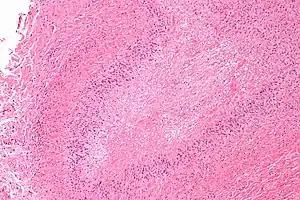

| Micrograph of a rheumatoid nodule, showing the characteristic palisading granuloma with a core consisting of necrotic collagen and fibrin. H&E stain. | |

Histological examination of nodules shows that they consist of a shell of fibrous tissue surrounding a center of fibrinoid necrosis.[11] Pea-sized nodules have one center. Larger nodules tend to be multilocular, with many separate shells or with connections between the necrotic centers. Individual necrotic centers may contain a cleft or several centers of necrosis may all open on to a large bursal pocket containing synovial fluid.

The boundary between the necrotic center and the outer fibrous shell is made up of the characteristic feature of the nodule, which is known as a cellular palisade. The palisade is a densely packed layer of macrophages and fibroblasts which tend to be arranged radially, like the seeds of a kiwifruit or fig.[11] Further out into the fibrous shell there is a zone that contains T cells and plasma cells in association with blood vessels.[12] The histology of pulmonary nodules are similar to that of subcutaneous nodules, with central necrosis surrounded by palisading macrophages and inflammatory infiltrate.[5]